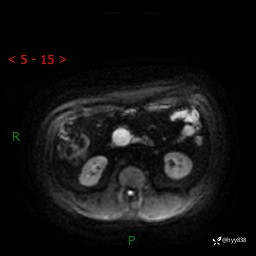

MRI(T1WI+T2WIfs+DWI)